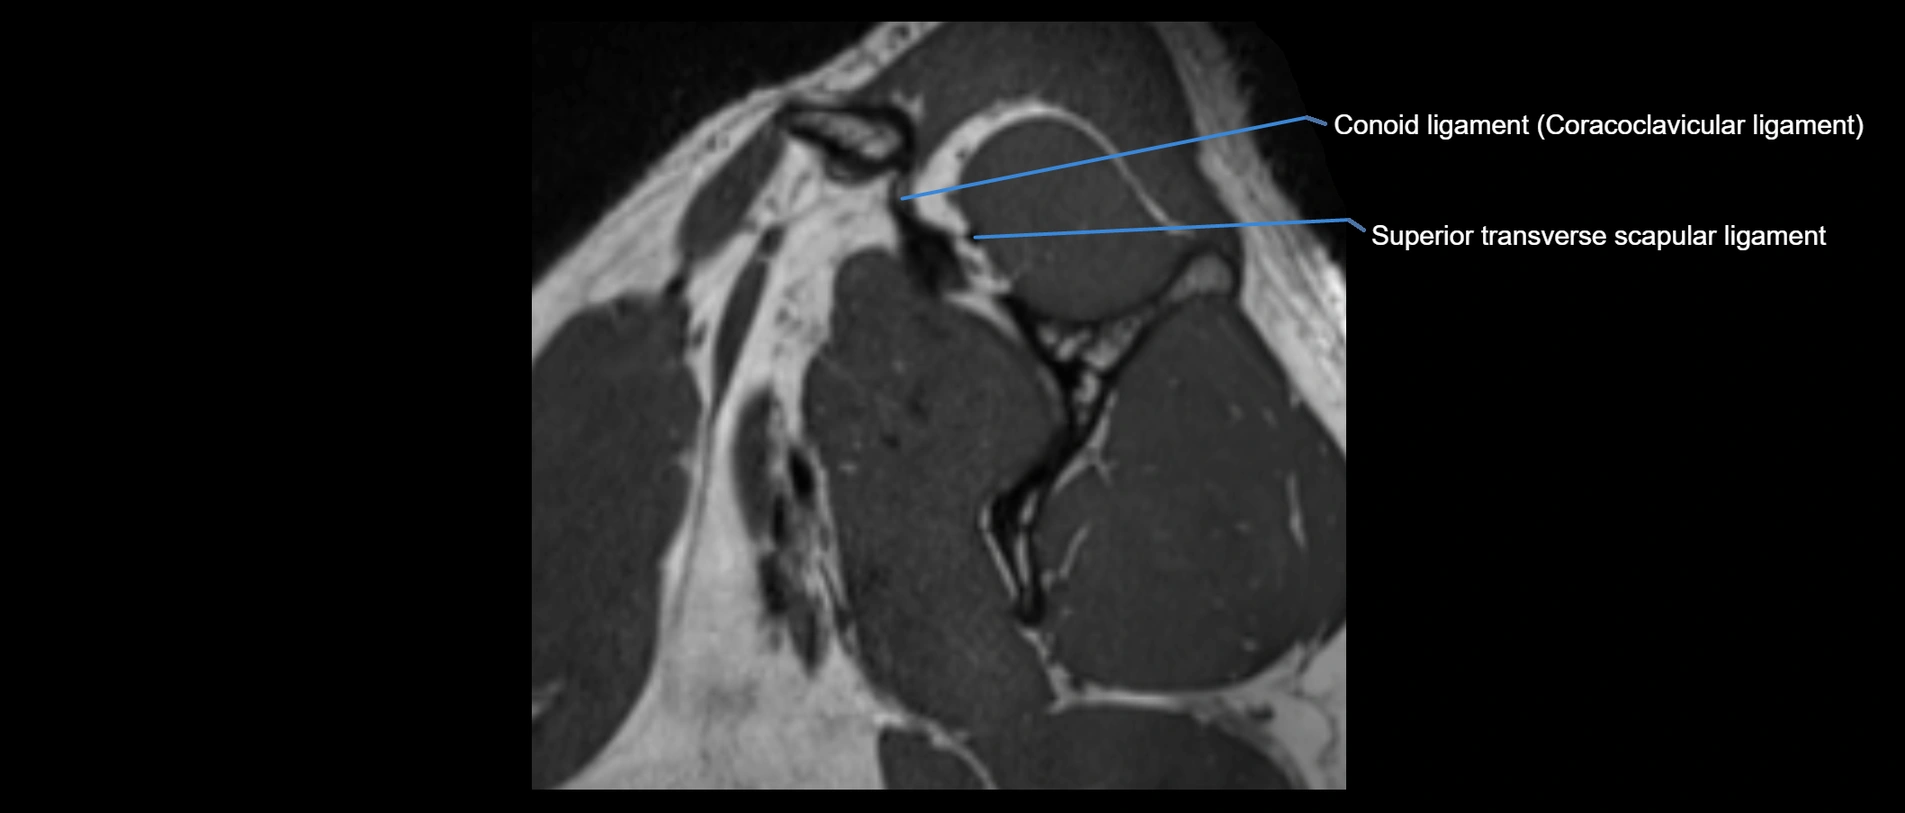

CT image

image